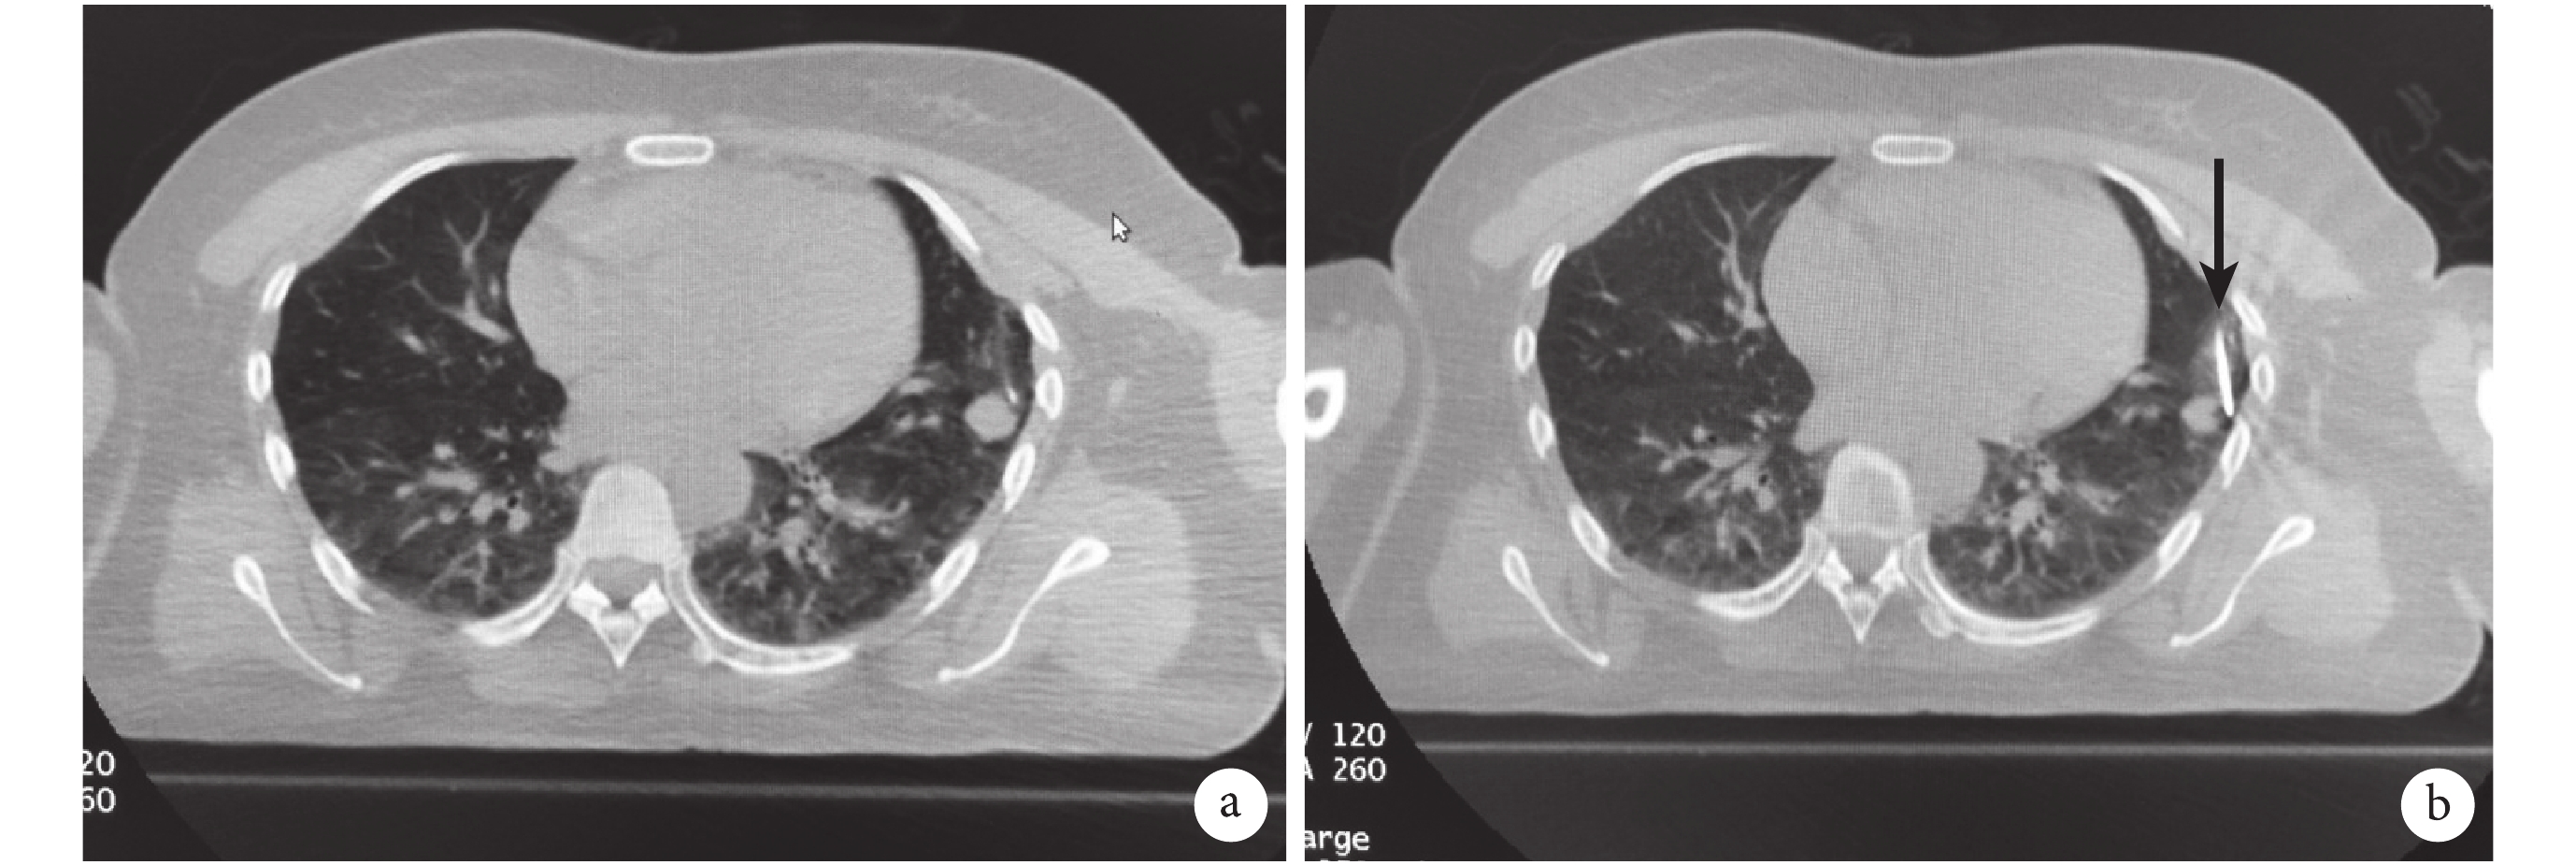

病例 2,男,80 歲,喉癌術后2年,頸動脈搭橋術后 1 年,有肺氣腫病史。CT 隨訪右上肺病灶增大 1 年,最長徑 7~13 mm,考慮為轉移性,擬行穿刺活檢同期微波消融治療。術前低分子肝素替代抗凝藥物 1 周,術前 24 h 停藥[20-21]。該患者轉移瘤影像學特征:一是病灶較小,長徑長,橫徑短,呈不規則長橢圓形(圖2a);二是患者有肺氣腫表現(圖2a~c),肺質地較差,綜合判斷穿刺后容易出現氣胸、出血等情況;三是瘤體周邊血供較豐富(圖2b~c),病灶上方與 1 支1.5 mm 較粗的特征性血管相連通(圖2b)。CT 定位下穿刺活檢第一針后,患者即出現了咳嗽、咯血癥狀,即刻 CT 掃描可見病灶周邊肺實質出現大片滲出影(圖2d)。由于患者劇烈咳嗽,造成瘤體在肺內活動度加大,且出血滲出遮蔽了病灶部分位置,消融針進針時偏向長橢圓形病灶的下方,進針后立即給予 50 W 5 min 熱消融,通過熱傳導止血后不久,患者咯血也即停止。由于消融針偏移且病灶上方血供豐富,很可能出現消融不完全的情況,因為血管內的血流不僅會帶走熱量,而且血管與腫瘤相連接的部位,很有可能出現血管浸潤性腫瘤擴散[22]。我們在瘤體上方特征性血管層面再次進針(圖2e),補充 45 W 3 min 微波消融,通過上下區域疊加消融,完成治療。

a:病灶較小,長徑長,橫徑短,呈不規則長橢圓形;b:瘤體上方有一條 1.5 mm 的特征性血管;c:瘤體周邊小毛刺,肺實質內可見氣腫泡;d:病灶周邊肺實質出現大片滲出影;e:在瘤體上方特征性血管層面再次進針疊加消融